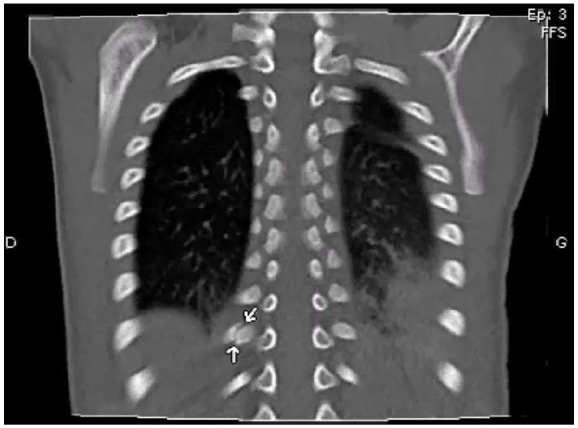

When Pneumococcal Infection Leads to Maltreatment Concerns.